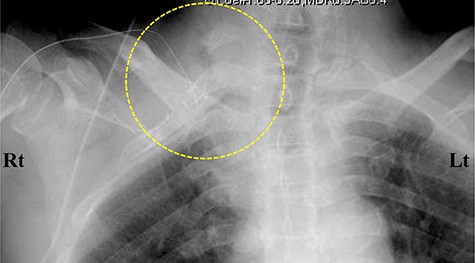

Three weeks after the onset of right-hand symptoms, he was treated with an emergency thrombectomy. The right subclavian arterial lumen was filled with an organized thrombus. After a few days of anticoagulation therapy (heparin 20 000 U/day) to prevent recurrent or new emboli, the pulse of the right radial artery could be felt, and the gangrene seemed to be reduced. One month after thrombectomy, surgical decompression was performed. After the scalenus anterior/medius muscle was dissected free from the first/second rib using the supraclavicular fossa approach, the high riding first rib was resected with the second rib (Fig. 5).

Postoperative cervicothoracic spine X-ray. Anterior–posterior view. The right first and second ribs were surgically resected (circle).